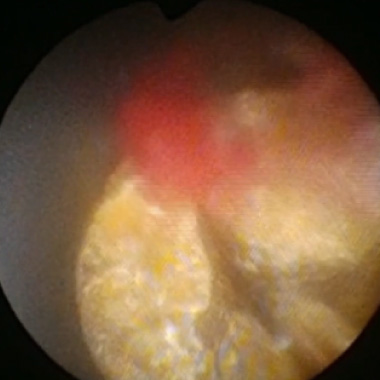

膀胱がん

早期がんに対しては内視鏡的切除術を施行しています。進行した膀胱癌に対しては、原則的には膀胱全摘術行い、尿道が温存できる場合には小腸で新しい膀胱を造り、自然排尿可能となる手術を行っています。また、膀胱温存を希望される場合には、内視鏡を使った手術と抗癌剤の注射と放射線治療を組み合わせた治療を選択します。